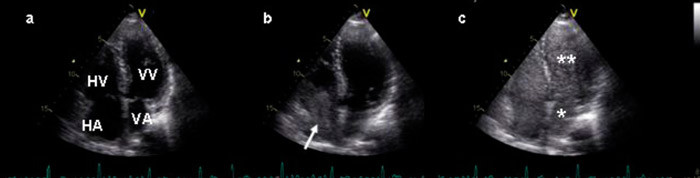

For å verifisere diagnosen hepatopulmonalt syndrom, måtte en eventuell shunting fremstilles visuelt og shuntstørrelse beregnes. Ekkokardiografi med saltvannskontrast kan benyttes for å påvise intrapulmonal eller intrakardial shunting (8). Kontrasten lages ved å løse 0,5 ml romluft fysikalsk i 9,5 ml fysiologisk saltvann, som så infunderes som bolus i en kubitalvene. Gassboblene i saltvannet vil normalt kun gjenfinnes i høyre hjertehalvdel, fordi de filtreres bort i lungekarsengen. Hvis det foreligger en høyre-venstre-shunt, vil gassbobler også gjenfinnes i venstre hjertehalvdel. For å skille intrakardiale og intrapulmonale shunter måles tiden det tar før gassboblene gjenfinnes i venstre hjertehalvdel. Ved en intrakardial høyre-venstre-shunt kan gassboblene ses i venstre hjertehalvdel innen tre hjerteslag etter at kontrasten har nådd høyre atrium. Hvis det foreligger en intrapulmonal shunt, vil det ta mer enn tre hjerteslag før gassboblene gjenfinnes i venstre hjertehalvdel.

Det ble utført ekkokardiografi med intravenøs saltvannskontrast (fig 3). Hos vår pasient ble det observert overgang av gassbobler fra høyre til venstre hjertehalvdel 4 – 5 hjerteslag etter injeksjon. Dette indikerte at det forelå en høyre til venstre intrapulmonal shunt. For å beregne shuntfraksjonen ble det utført nukleærmedisinsk scintigrafi med intravenøs injeksjon av 99mTc-MAA, og deretter registrering av helkroppsscintigrammer fra ventral- og dorsalsiden. Gjennomsnittsverdi forfra og bakfra ble beregnet til 25 %, altså en signifikant shunting og i overensstemmelse med visuell bedømmelse av scintigrammene.